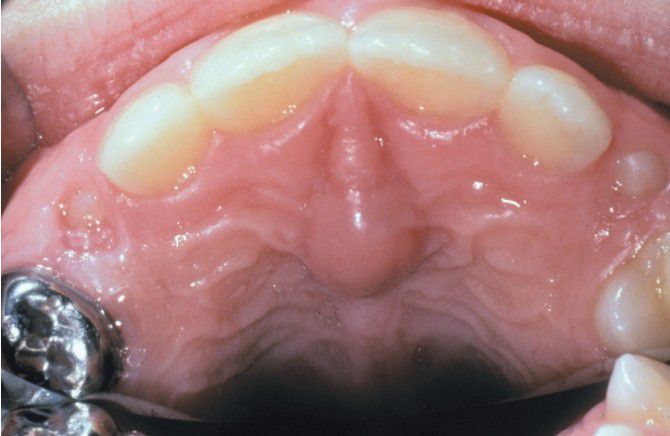

Cyst of incisive papilla

Cyst of the Incisive Papilla. Swelling of the incisive papilla.